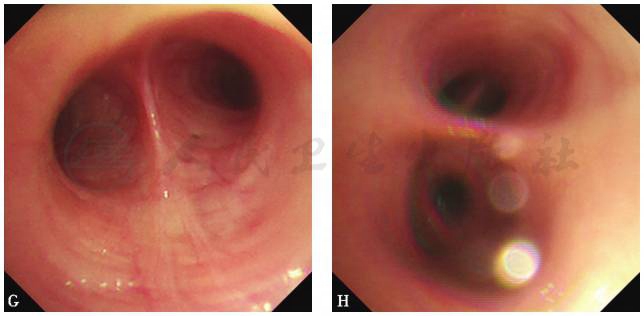

【气管镜检查】

支气管镜下表现:可见部分支气管黏膜下毛细血管扩张,未见其他异常(图7)。

支气管肺泡灌洗液(右中肺内侧段):细胞总数0.31×106/ml;其中,巨噬细胞72%,淋巴细胞23%,分叶核细胞5%,嗜酸性粒细胞0%,嗜碱性粒细胞0%;普通细菌涂片偶见革兰阴性菌;真菌涂片未找到真菌菌丝;浓缩抗酸杆菌阴性。

A.气管隆嵴;B.左主支气管;C.左上叶支气管;D.左下叶支气管;E.右上叶支气管;F.右中间段支气管;

G.右中叶支气管;H.右下叶支气管

图7 气管镜检查镜下表现